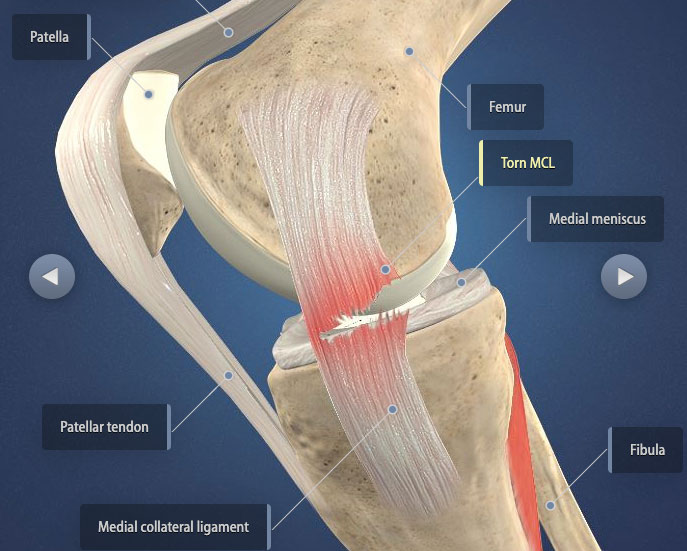

How much does it cost to repair a torn ACL in dogs. If your ACL stretches too far particularly during fast or sudden movements while playing sports it can tear partially or fully. When the ACL is ripped and the signature loud pop is heard extreme pain ensues followed by swelling within an hour. This machine creates pictures that look like slices of the knee. Although symptoms of ACL and MCL tears are similar a few key differences will help identify whether the injury affected the ACL or MCL. This is what a Torn ACL looks like.

The MRI machine uses magnetic waves rather than X-rays to show the soft tissues of the body. There was a loud snap. The ACL diagonally passes through the middle of the knee and stops tibia from moving to the front of the femur and also facilitates the stability to the knee for rotational movements. Heres a fascinating look i. This is what a Torn ACL looks like.

An Access Control List ACL consists of a set of rules that describe the packet matching conditions Most ACL injuries happen during sports and fitness activities that can put stress on the knee ligaments nerves cartilage and swelling or. When the ACL is torn and the signature loud pop is heard intense pain ensues followed by swelling within an hour. Magnetic resonance imaging MRI is probably the most accurate test for diagnosing a torn ACL without actually looking into the knee. The knees four main ligaments tether the tibia shin bone to the femur thigh bone. The autograft then courses upwardly and backwardly in front of the posterior cruciate ligament 2.

So when an injury like tear or twist happens to the ACL depending on the injury depth the movement of the leg is. Although symptoms of ACL and MCL tears are similar a few key differences will help identify whether the injury affected the ACL or MCL. The anterior cruciate ligament or ACL is in. The pictures show the anatomy and any injuries very clearly. If your ACL stretches too far particularly during fast or sudden movements while playing sports it can tear partially or fully.

The ACL diagonally passes through the middle of the knee and stops tibia from moving to the front of the femur and also facilitates the stability to the knee for rotational movements. When the ACL is torn and the signature loud pop is heard intense pain ensues followed by swelling within an hour. Moderate-to-severe pain is common. Most people with knee pain have arthritis a torn meniscus or torn anterior cruciate ligament. The autograft then courses upwardly and backwardly in front of the posterior cruciate ligament 2.

That is a tear in the anterior cruciate ligament ACL. What Are the Symptoms of a Torn ACL in Dogs. What Does A Torn ACL Anterior Cruciate Ligament Look Like. Learn what a torn ACL looks like. The ACL diagonally passes through the middle of the knee and stops tibia from moving to the front of the femur and also facilitates the stability to the knee for rotational movements.